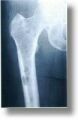

Knochenstoffwechselerkrankungen wie die Osteoporose haben wesentliche

Auswirkungen auf die Statik und Dynamik der Stütz- und Bewegungsorgane.

Neben der entsprechenden Diagnostik (z. B. Knochendichtemessung) und der

medikamentösen Therapie mit modernen Osteoporosemitteln besteht der

therapeutische Ansatz in erster Linie in der lokalen Schmerzbehandlung

und Hilfsmittelversorgung. Eine enge Zusammenarbeit mit anderen Fachdisziplinen

wie der Gynäkologie ist erforderlich.